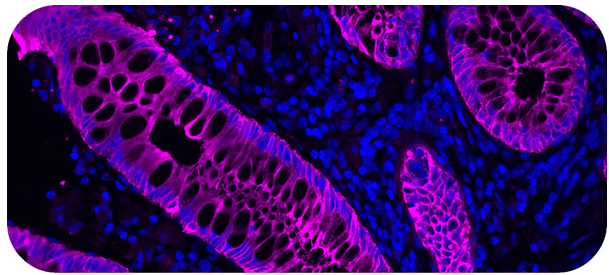

Immunofluorescence

Empowering discovery with functionalized tools for fluorescence-based detection

Complete Solutions for Your Immunofluorescence Workflow

Vector Laboratories’ portfolio of immunofluorescence (IF) reagents optimize every step of the process.

With reagents that streamline antigen retrieval to preserving mounted tissue samples, their catalog supports the IF workflow from start to finish.

They also offer functionalized solutions for challenges like species-on-species detection and multiplexing so researchers can achieve exceptional sensitivity,

specificity, and reproducibility in even the most advanced IF applications.